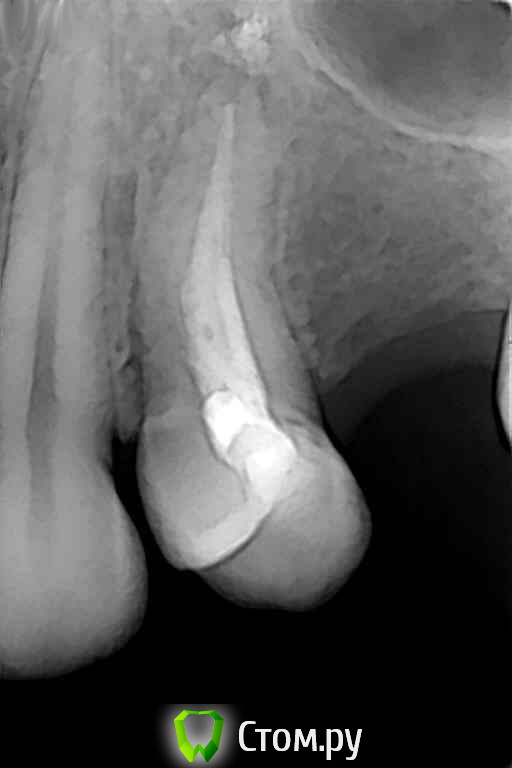

Михаил Демурчян Опубликовано 29 октября, 2014 Поделиться Опубликовано 29 октября, 2014 (изменено) Комментарии к фотографиям: 1. В тех случаях, когда нужно поднять пазуху всего на 2-3 мм, можно обойтись совершенно без остеопластического материала. Рентгенограмма до операции. 2. Рентгенограмма сразу после операции. Над установленным имплантатом виден фрагмент кости вследствие проведенной остеотомии. Тень полусферы обозначает границы кровяного сгустка под слизистой оболочкой пазухи. 3. Контрольный снимок спустя год после операции. Видна новая граница пазухи над имплантатом. Изменено 29 октября, 2014 пользователем Михаил Демурчян 4 Ссылка на комментарий